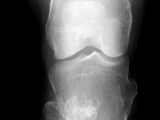

Multiple hereditary exostoses-knee

Multiple hereditary exostoses-knee